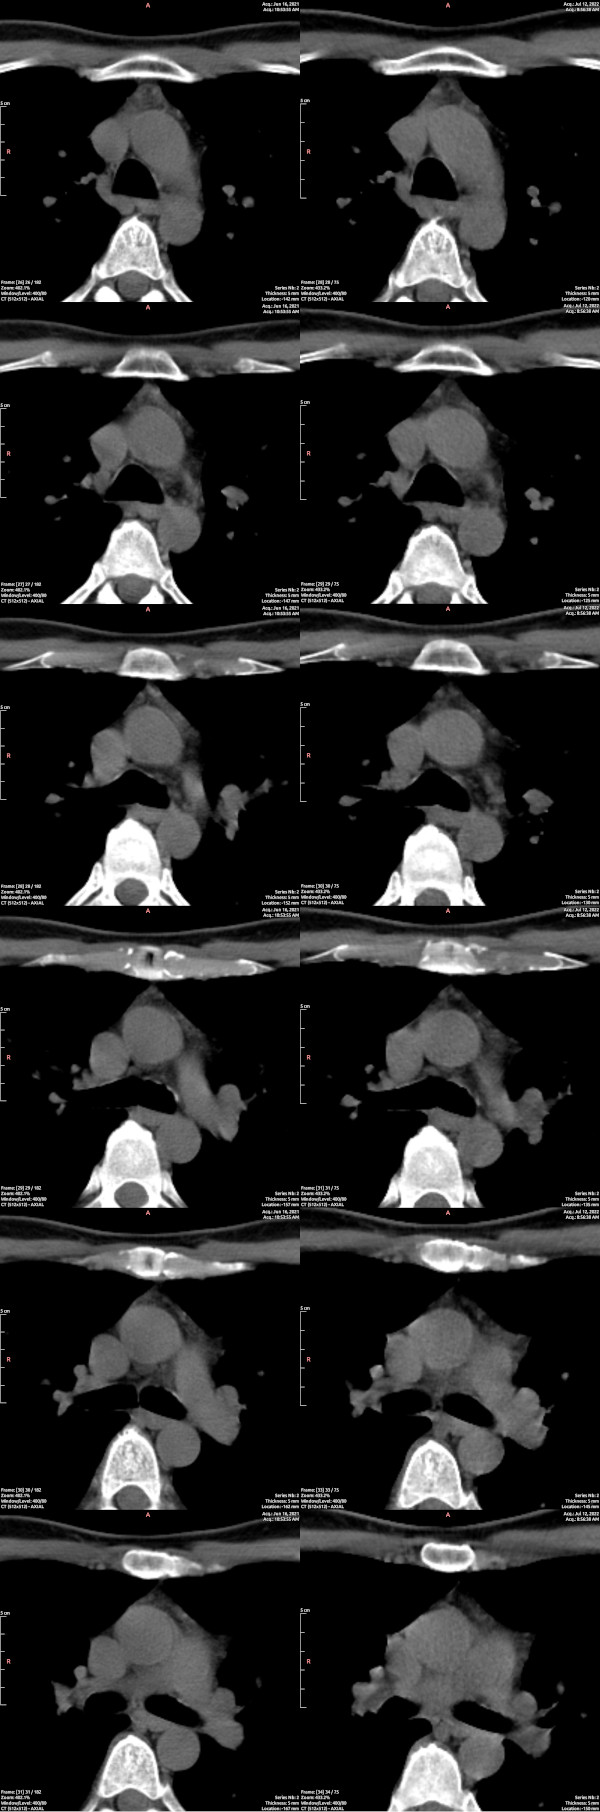

CT images of the thymus showed a visible reduction in active tissue across the nine months of the study, the opposite of the hoped outcome. In the image below, paired cross-sections through the chest are shown, before on the left, after on the right. For guidance on reading CT scans of the thymus, refer to “Normal Thymus in Adults: Appearance on CT and Associations with Age, Sex, BMI and Smoking“. In a cross-section of the chest, as below, and as in the examples given in that paper, the thymus is the triangular patchy grey structure closer to the top of the image, immediately below the sternum (white). Areas of fat will appear dark in the range chosen here, and thus a more atrophied thymus, in which more active tissue is replaced with fat, will appear darker. By late life, the thymus is entirely dark, fatty.